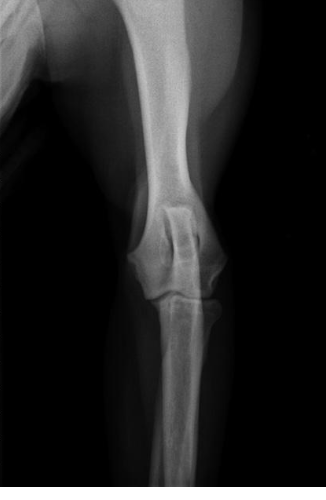

what position do we put the animal in if we want a cranio-caudal view of the elbow?

sternal recumbency with the forelegs extended cranially

what radiographic view of the elbow is shown?

cranio-caudal view